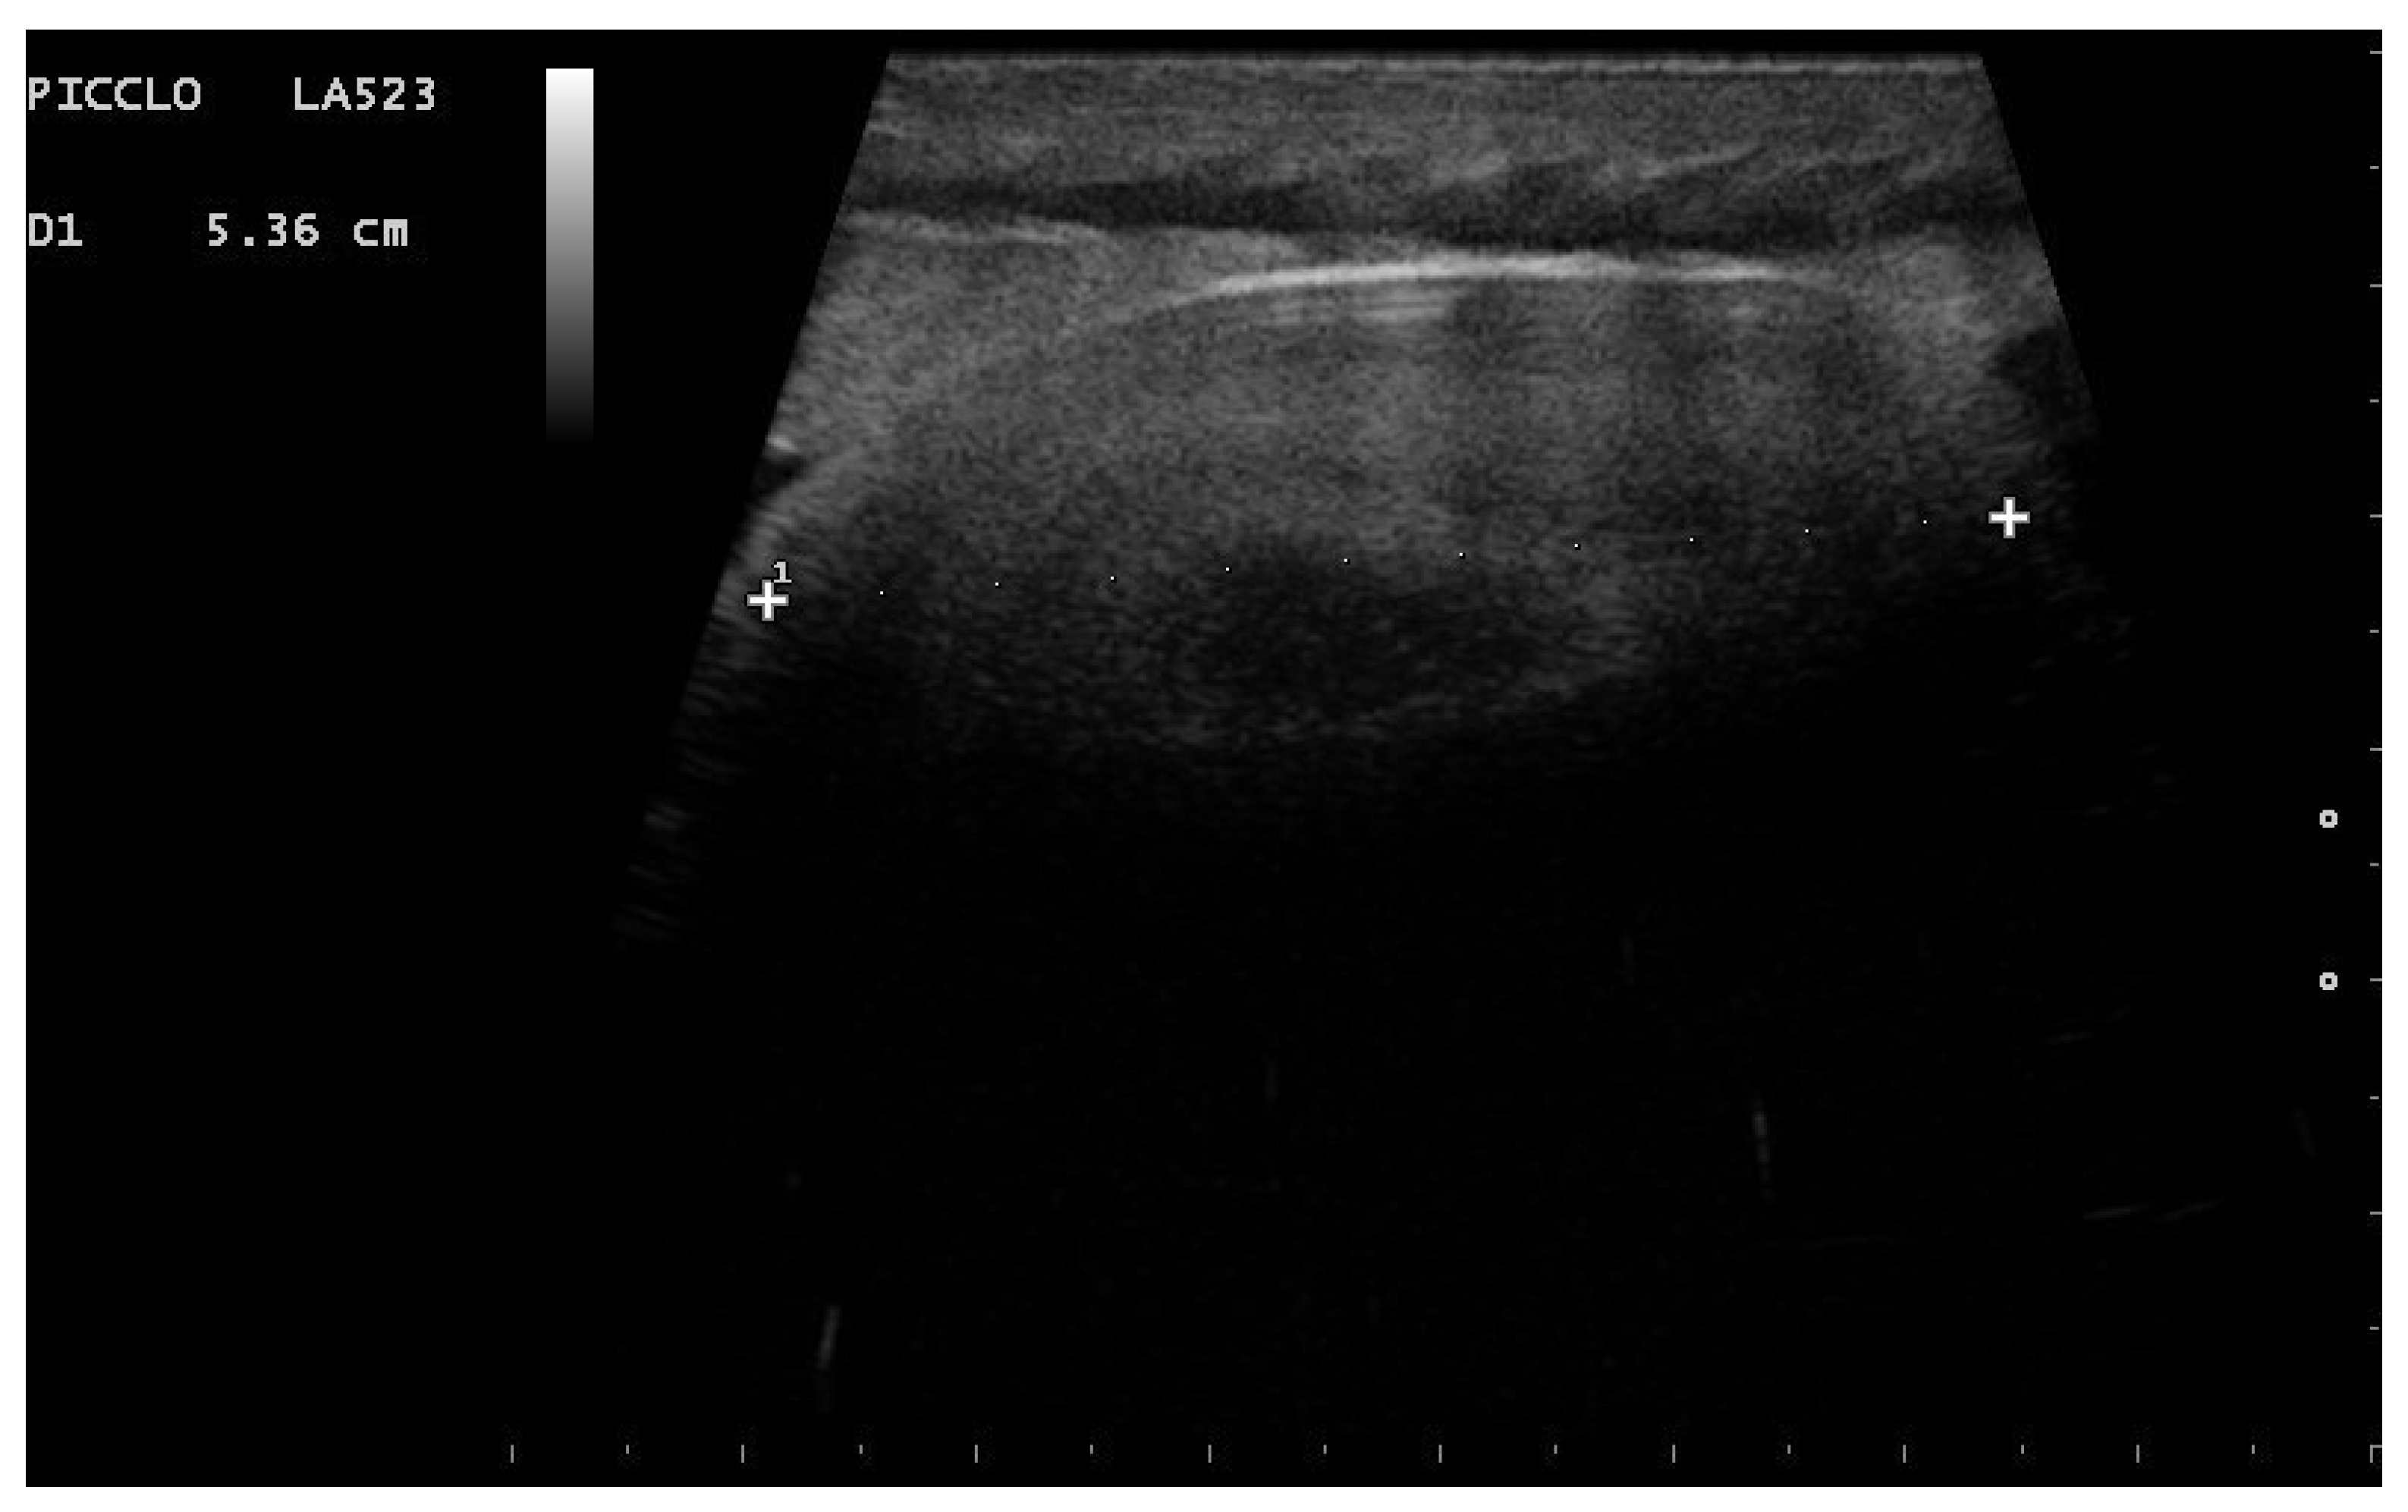

- Garcia, V.C.; Almeida-Santos, S.M. Reproductive cycles of neotropical boid snakes evaluated by ultrasound. Zoo Biol. 2021, 1–10. [Google Scholar] [CrossRef]

- Isaza, R.; Ackerman, N.; Jacobson, E.R. Ultrasound imaging of the coelomic structures in the Boa constrictor (Boa constrictor). Vet. Radiol. Ultrasound 1993, 34, 445–450. [Google Scholar] [CrossRef]